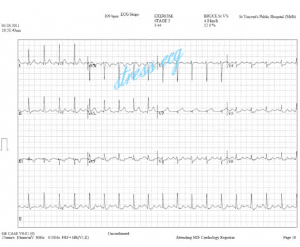

ストレスecgは、簡単に言えば、トレッドミルにECGモニターを装着し、徐々に加速してジョギングを行い、ECGの変化を観察します。つまり、運動量を徐々に増やすことで、心臓のエネルギー消費量が増加します。これは、冠状動脈疾患の患者の運動負荷です。条件下でのECGパフォーマンス。

これは、冠状動脈性心臓病の診断に最も一般的に使用される補助診断テストの1つです。stress ecgは、患者の心臓機能をチェックして、彼の作業能力、病気の程度を測定したり、治療の効果を評価したりすることができます。